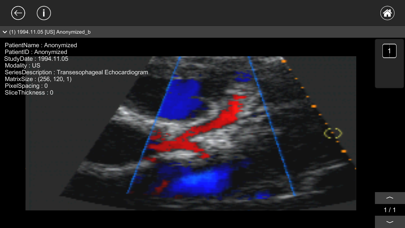

MR、CT、SPECT、PET、X線、超音波などで撮影された医用画像(DICOM画像)を閲覧することができます。

※スクリーンショットで使用しているDICOMデータおよび患者名は架空のものです。

MR、CT、SPECT、PET、X線、超音波などで撮影された医用画像(DICOM画像)を閲覧することができます。

※スクリーンショットで使用しているDICOMデータおよび患者名は架空のものです。